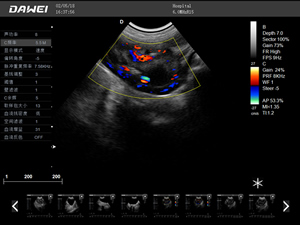

·支持彩色多普勒、頻譜多普勒、能量多普勒、連續多普勒等成像技術

·實時三維成像技術